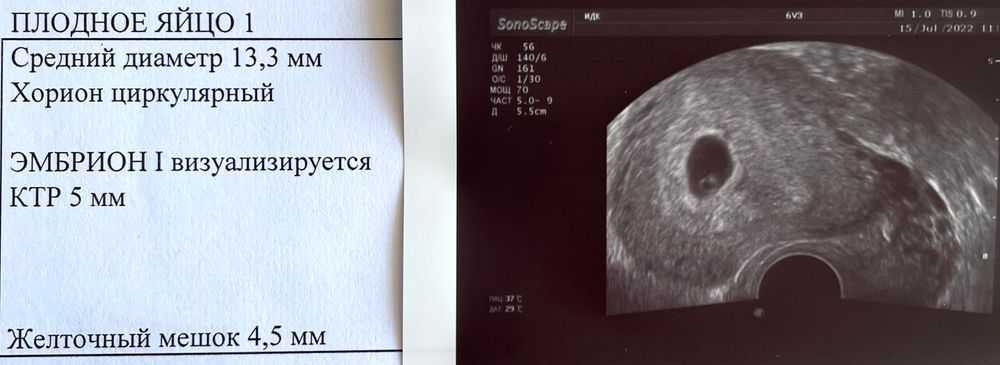

здравствуйте! я вера была на узи, 6+1) тоже такой же ктр, сердцебиение послушали) пусть всё у нас будет хорошо)